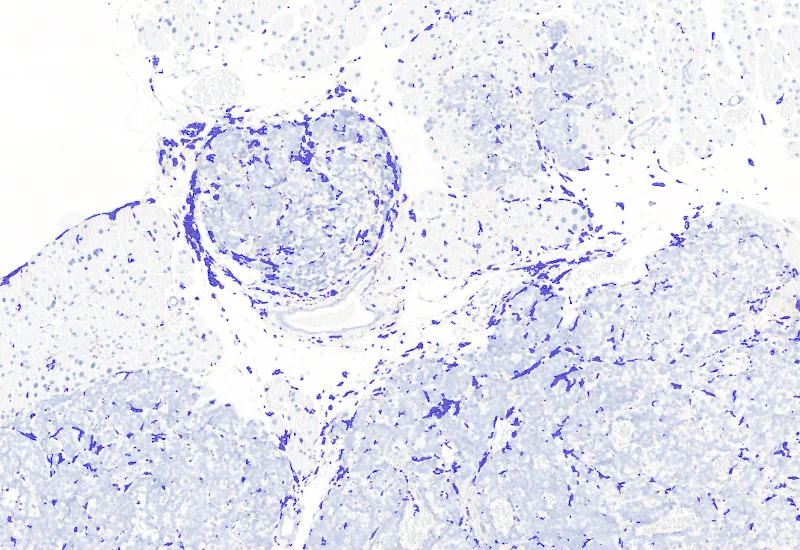

Macrophage detection

The IHC Tumor-Macrophages APP provides tissue detection including separation into tumor tissue and healthy tissue. It detects macrophages based on a specific staining (e.g. CD68). The APP outputs the area of macrophages within tumor tissue and healthy tissue.

Segment tissue into tumor and healthy areas, detect CD68+ macrophages, and quantify macrophage area within each tissue compartment.